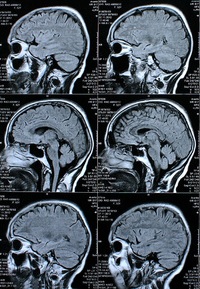

Schnittbilder: Forscher ergründen Gedächtnis (Foto: pixelio.de, rike) |